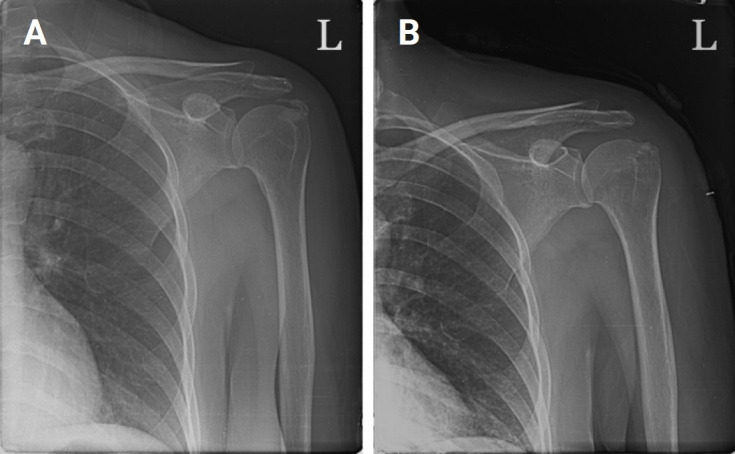

We present a case of calcific tendinitis in the shoulder, where calcifications were observed within both the tendon and the adjacent bone. At the time of acute onset, radiographs (including a plain radiograph) and magnetic resonance imaging revealed calcific tendinitis with intraosseous migration. The patient's symptoms did not improve after 5 months of conservative treatment. The patient underwent arthroscopic debridement of the calcific deposits, and the defect was repaired using the double-row repair technique. The patient's symptoms improved 3 months after arthroscopic treatment. We share our unusual experience with arthroscopic debridement in the treatment of chronic calcific tendinitis with intraosseous migration.